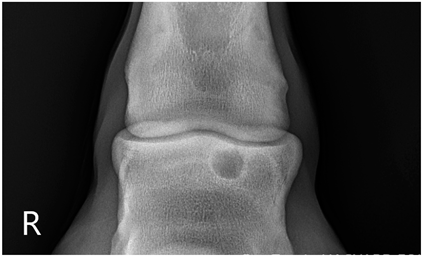

2.2. Image Analysis

Preoperative radiographs in DICOM format were evaluated blindly in a randomized order by three observers using medical imaging viewer software (OsiriX® Lite v12.0.1 DICOM viewer, Pixmeo SARL, Bernex, Switzerland). The width and height of the lesions were measured in dorsopalmar/plantar radiographic views. The magnification was corrected by calculating the index of the measured SCL with the total width of the specific joint affected. Each measurement was taken once by three authors. The mean of the three different measurements was calculated and used for statistical purposes. SCL shape was classified in three categories, following previous classification guidelines (Table 1 and Table 2) [8]. The intraclass correlation coefficient was calculated to make sure that there was a high level of agreement between observers when taking height and width measurements and when classifying SCLs by shape.

The median and interquartile ratios of the SCL height and width were 9.47 mm (6.97–10.92 mm) and 8.58 mm (6.98–10.96 mm), respectively. The SCLs located in the distal metacarpal/metatarsal bones measured 9.03 mm (6.96–10.9 mm) in height and 8.52 mm (7–10.92 mm) in width. A more oval shape was found in the lesions of the proximal phalanx, with a median height of 10.8 mm (7.03–10.95 mm) and a median width of 7.78 mm (7.09–10.96 mm). A rounder shape was found in the distal phalanx, with a median of 10.28 mm (7.05–10.97 mm) for height and 10.81 mm (7.03–10.95 mm) for width. The different bones affected by the SCLs were no different in the horse’s ability to start a race (p = 0.33).

Table 1. Radiographic appearance and shape classification into 3 types of subchondral lucencies based on their shape and communication with the joint.

Type 1Subchondral lucency with a dome shape and an articular surface defect of similar width as the middle of the lesion.Animals 13 02838 i001

Type 2Subchondral lucency with narrow communication with the joint surface (narrow cloaca) and round, wider lucency deeper in the bone.Animals 13 02838 i002

Type 3Subchondral lucency with no radiographic evidence of communication with the joint surface.Animals 13 02838 i003